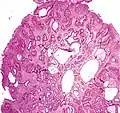

| Juvenile Polyp | Upper GI tract and colon | Cystically dilated glands with expanded lamina propria | Not inherently, may develop dysplasia | ![]() |

Juvenile polyposis syndrome, identical polyps in Cronkhite–Canada syndrome |